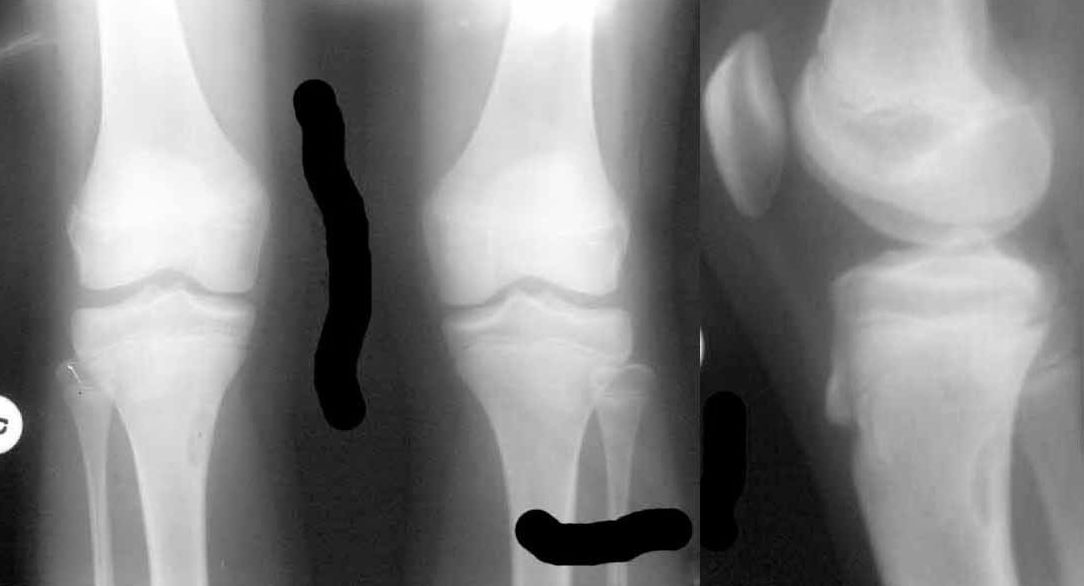

[Ortho] очаг фиброза в правой большеберцовой кости

"Девочке сейчас 12.5 лет,

Летом этого года стартовал пубертат, начала вытягиваться. В течение лета были активные физические нагрузки, в августе - длительные пешие походы в горах. С сентября стали появляться боли в коленных суставах, связанные с подъемом по лестнице и при приседании. Боли непостоянные, то в одной, то в другой ноге, иногда одновременно в обоих коленях. В покое и при обычной ходьбе боли не отмечаются.

18.01.2011 сделали снимки коленных суставов – выявлен очаг фиброза в правой большеберцовой кости?"

Что это?